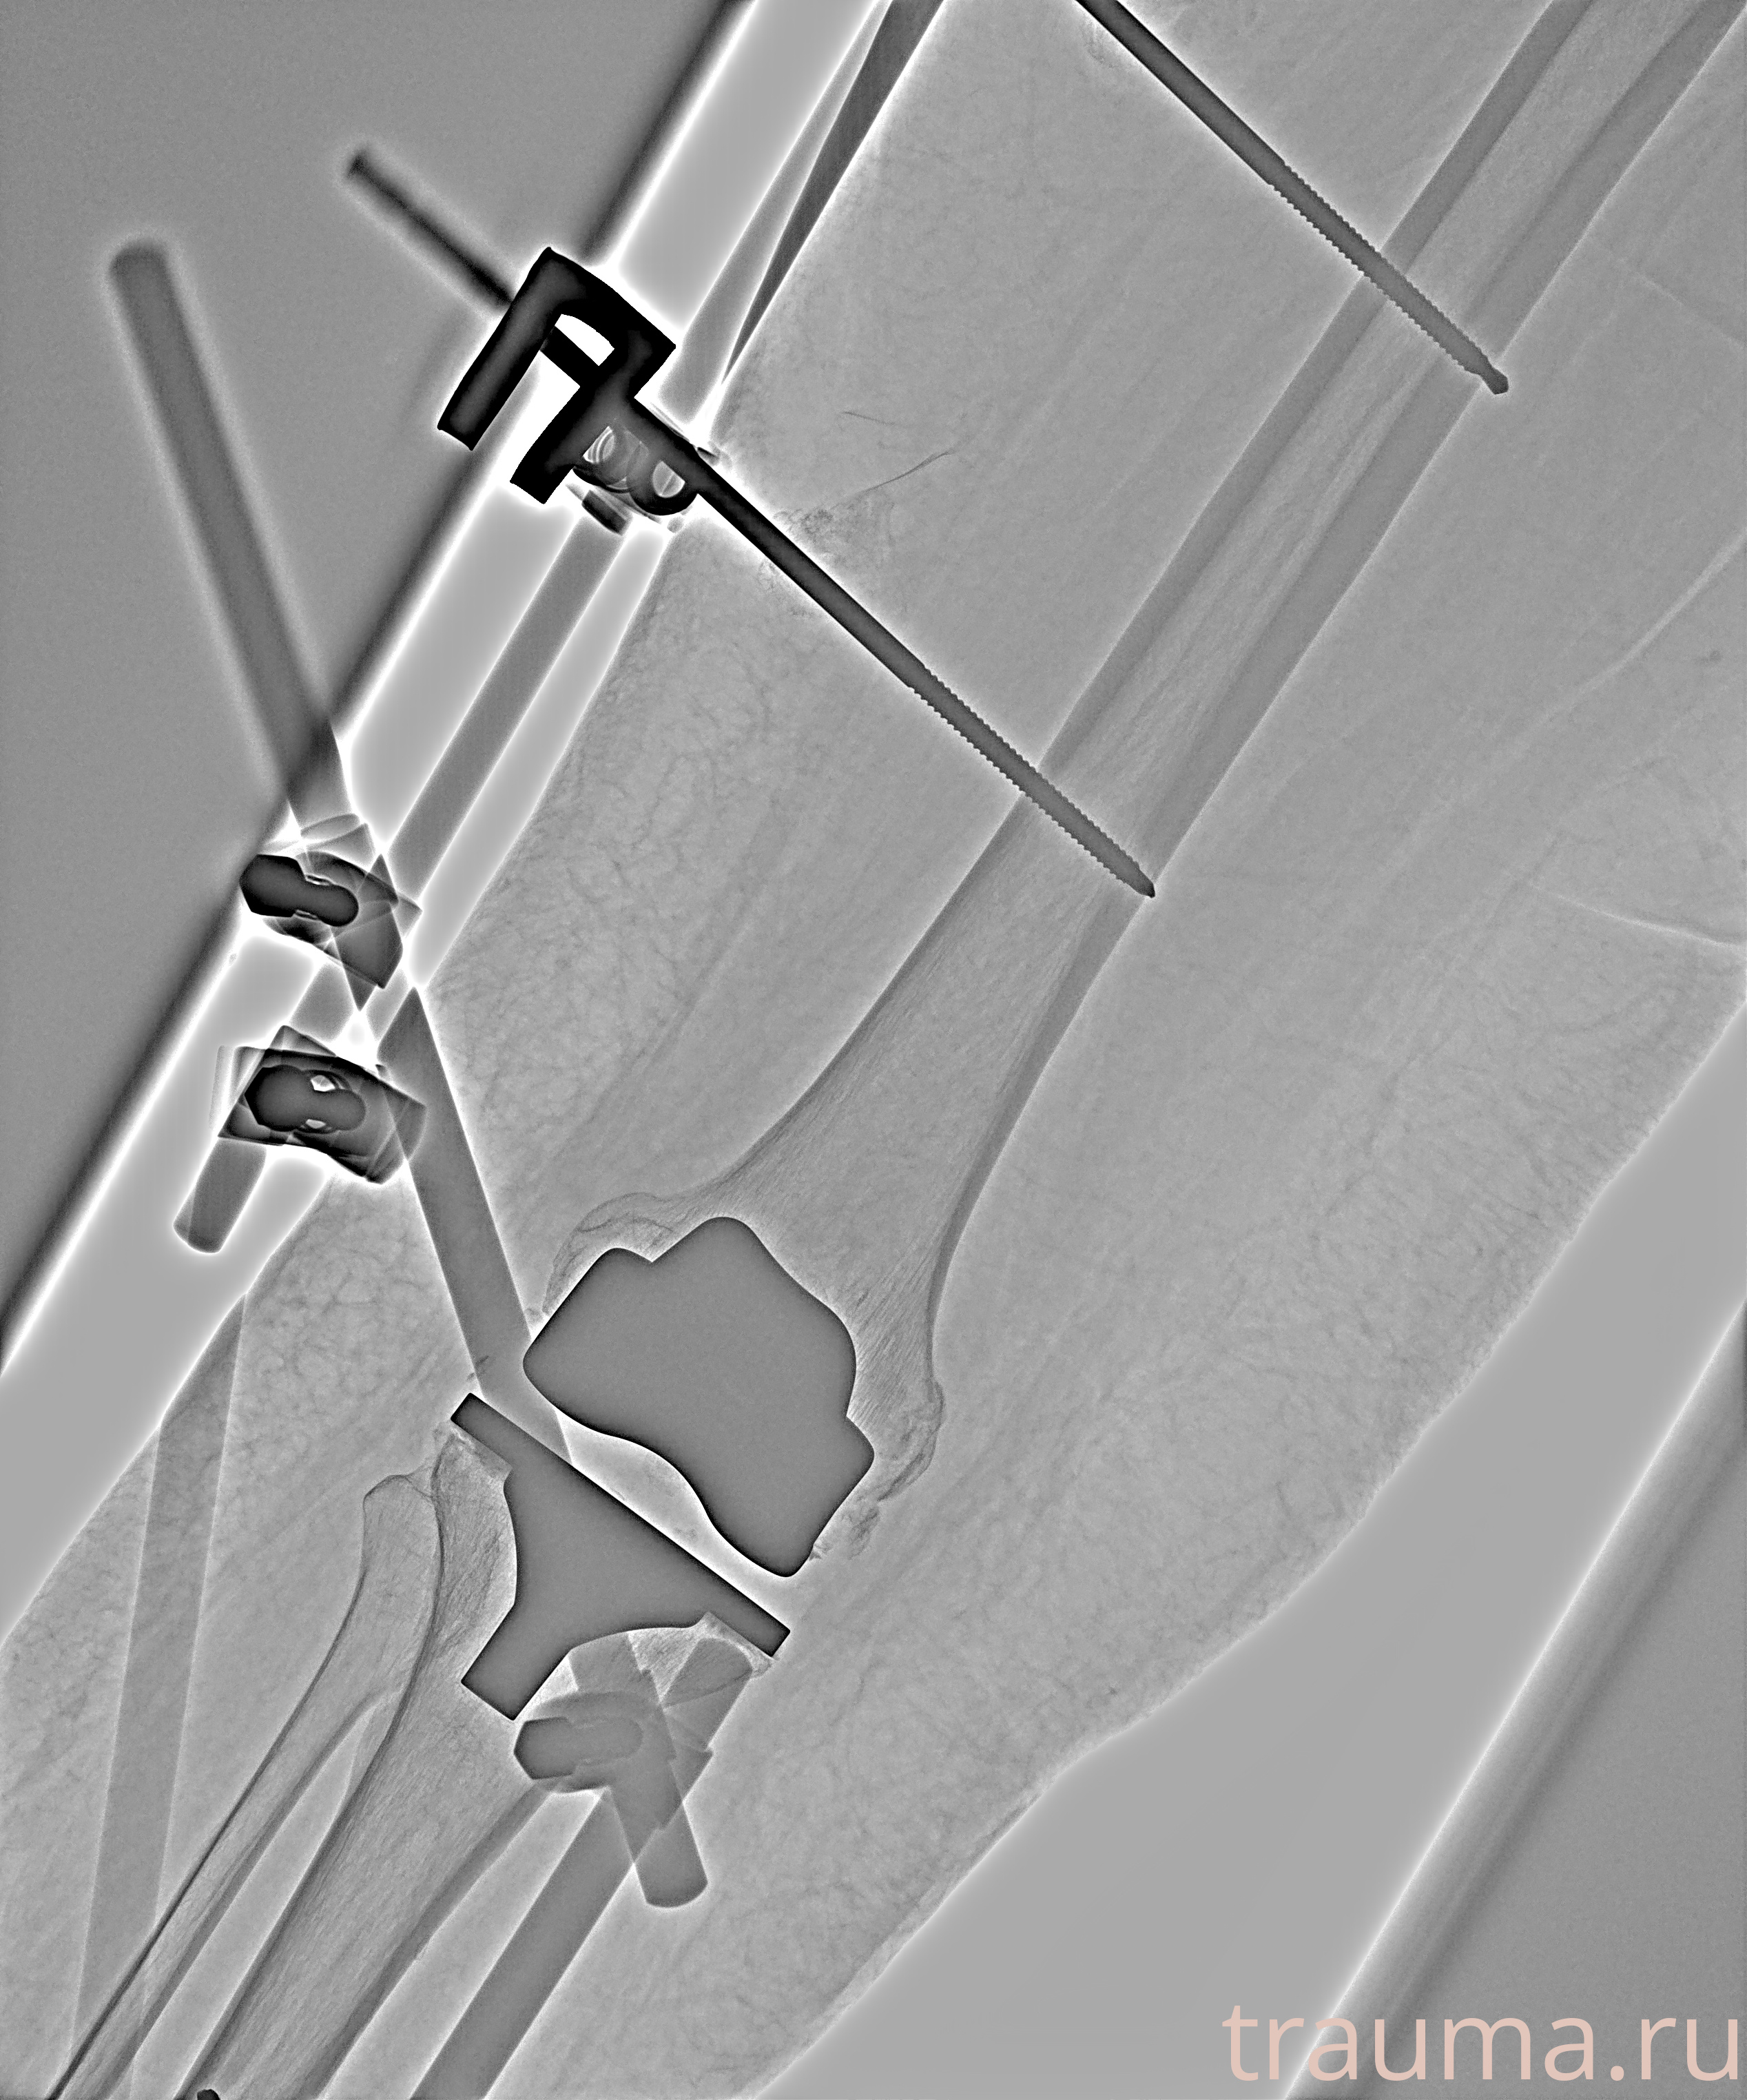

Рентгенограммы

Рентген на дому: по вашему адресу приезжает врач-рентгенолог, травматолог-ортопед с мобильным рентгеновским аппаратом, проводит диагностику травмы или заболевания, делает необходимые рентгенограммы, дает рекомендации по дальнейшему лечению. Получить качественные снимки в домашних условиях возможно благодаря уникальной методике, разработанной МосРентген Центром для института  Склифосовского